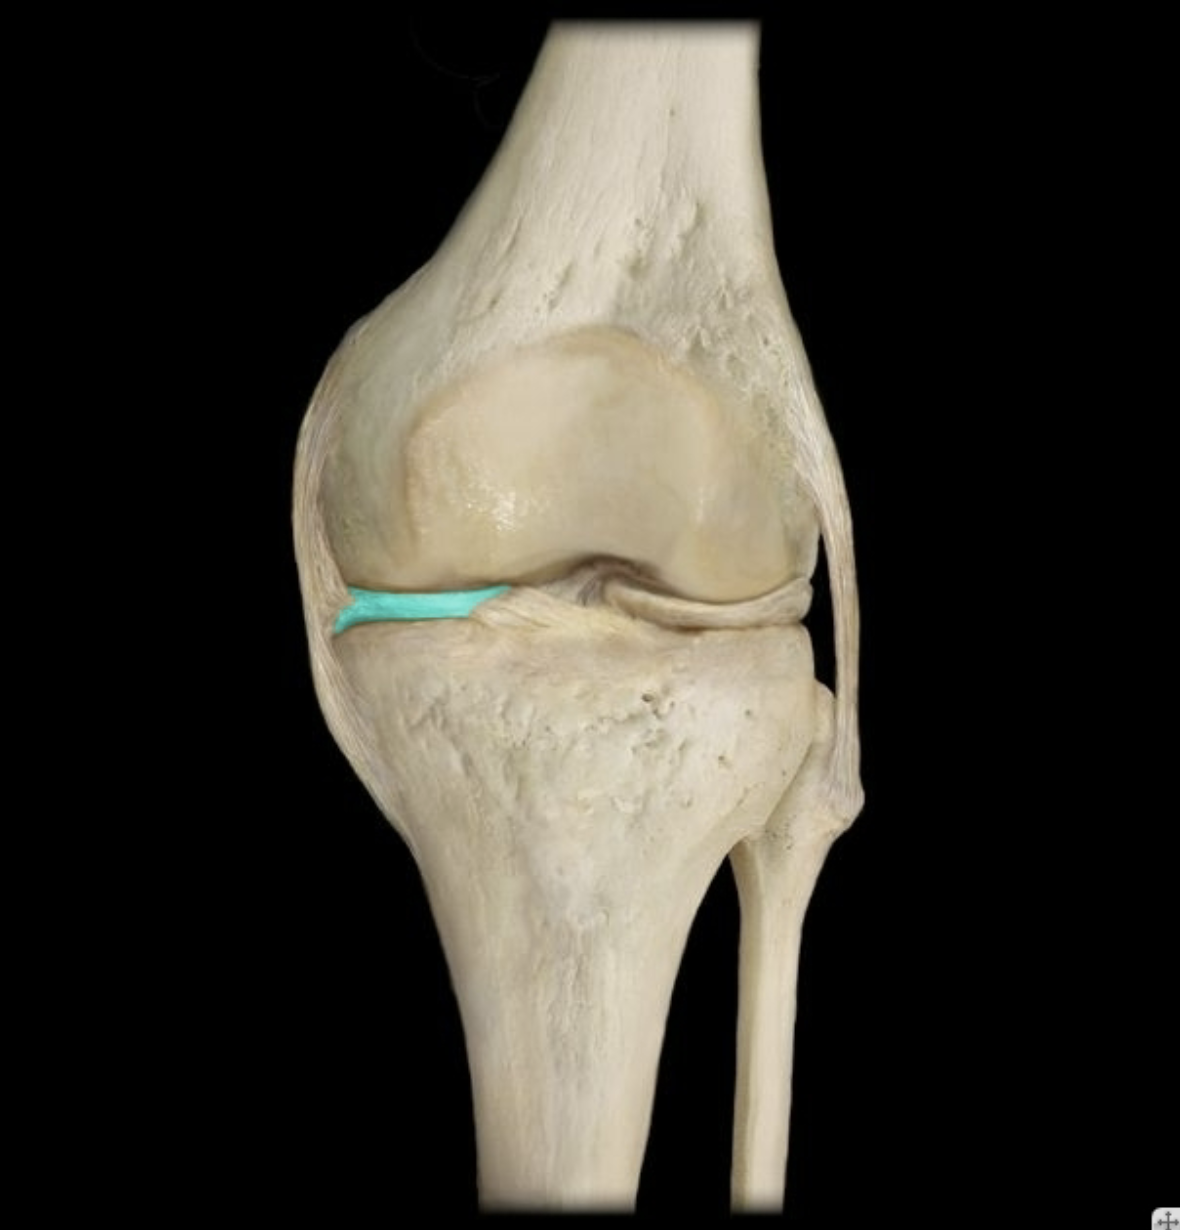

Medial collateral ligament

Lateral collateral ligament

Medial meniscus

Lateral meniscus